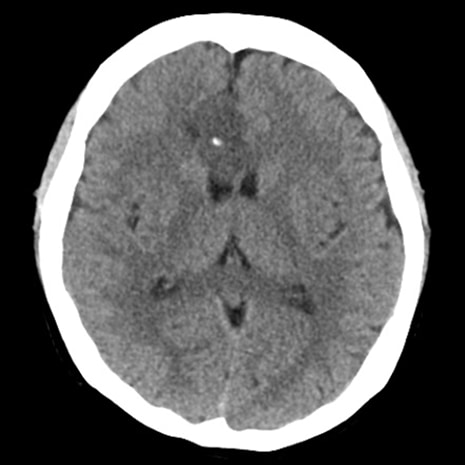

回転性めまいで救急搬送された患者。左上脱力あり。脳卒中を疑いCT/MRI検査したところ、右前頭葉に石灰化を伴う腫瘤を認めた。後日術前精査目的で造影MRI施行となった。

T1WI低信号、T2WI高信号、FLAIR高信号、DWIでやや高信号の腫瘤。Gdで腫瘤は造影されず、DSC-Perfusionでは辺縁~中心部に一部血流の高い部分あり。MRスペクトロスコピーではCho上昇とNAA低下がみられる。Low grade gliomaを疑う。後日、摘出手術が施行され、病理診断はoligodendroglioma NOS(Grade 2)であった。